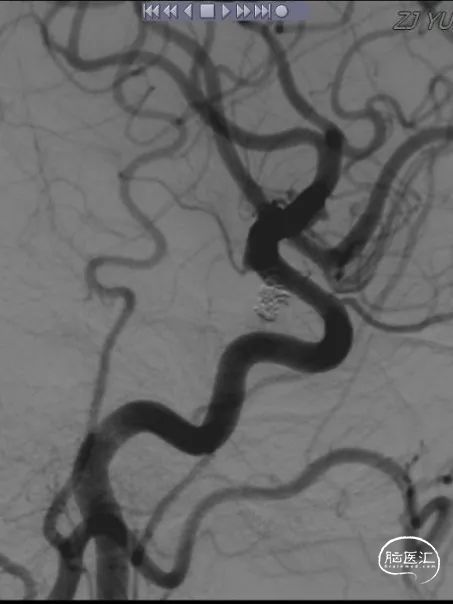

病史简介:患者女性,56岁,主因“发现右侧脑动脉瘤3月余”入院。查体神经系统阴性。3个多月前因“突发头痛、头晕3小时,神志不清2.5小时”伴有呼吸困难。被120送至我院急诊,予以行气管插管。急查CT提示“蛛网膜下腔出血”(图1)。头颅CTA提示“双侧颈内动脉C7段动脉瘤”(图2)。根据动脉瘤形状及CT蛛网膜下腔出血情况判断左侧脑动脉瘤为责任。遂急诊在全麻下行“DSA全脑血管造影术+支架辅助下左侧颈内动脉动脉瘤栓塞术”(图3)。手术经过顺利。术中同时发现右侧颈内动脉颈段冗长,迂曲严重,后交通动脉段亦见一动脉瘤,当时未做治疗。术后行“腰椎穿刺腰大池置管脑脊液引流术”。术后予护胃、营养神经、预防脑血管痉挛、脱水降颅压、抗感染、化痰、控制血压等对症治疗。术后康复出院。

图3

DSA示:右侧颈内动脉后交通动脉段动脉瘤,右侧颈内动脉冗长,迂曲严重,左侧颈内动脉后交通动脉段动脉栓塞术后。

在微导管及0.014微导丝的导引下,小心避开假腔,将中间导管(6F 115cm,中天天巡远端通路导管)顺利通过迂曲的颈内动脉,输送至颈内动脉床突段。在路图中见后交通段见一动脉瘤,大小约3.10mm×1.73mm。

术后造影复查显示:弹簧圈致密充填瘤体内,瘤体内未见造影剂充盈,支架位置完全覆盖动脉瘤,贴壁良好,右侧颈内动脉及大脑中、前动脉均显影良好。小心撤出栓塞微导管及支架微导管,撤出各级导管,结束手术。